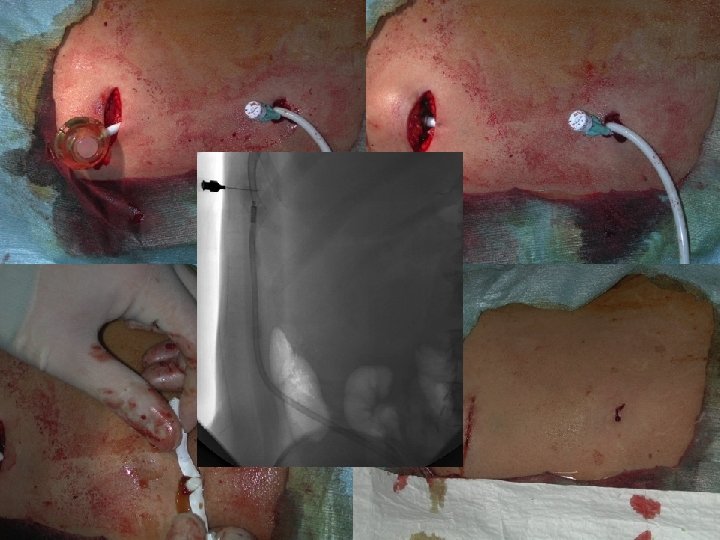

Peritoneal Port � Tünelli peritoneal kateterin alternatifidir. � Kozmetik olarak daha uygundur. � Tıkanma, malpozisyon, kink gibi katetere bağlı komplikasyonlar daha fazladır. � Fibrin kılıf oluşumu ciddi dezavantajıdır. (t-PA) � Barsak perforasyonu, port cebi enfeksiyonu ve peritonit geç komplikasyonlardır. � Over kanserinde intraperitoneal kemoterapi için terapötik kullanımı da vardır.

Peritoneal Port Angiodynamics Bard